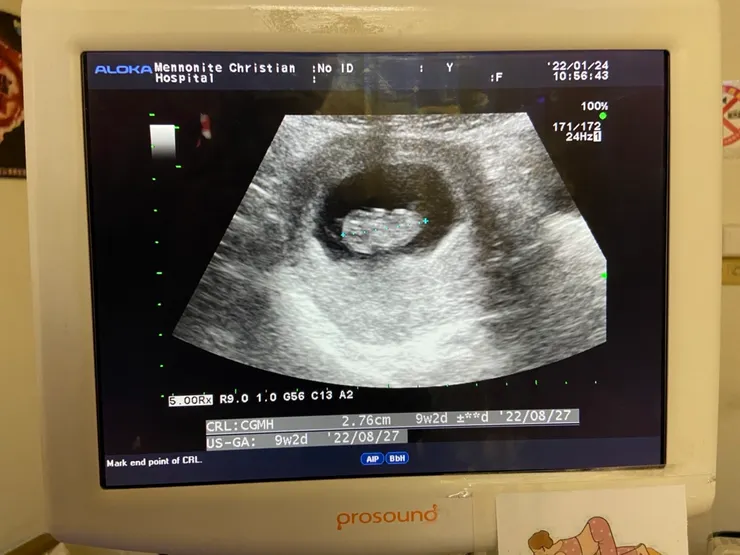

「我懷孕了。」

記於2022/4/22 22w2d